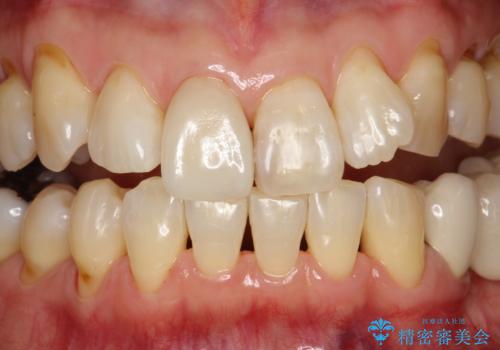

専門的な機械や材料を使用し、60分コースのPMTCクリーニングで、全体的な歯石や着色の除去を行いました。

PMTCは、毎日のブラッシングや食事によって傷ついた歯をツルツルでなめらかにします。継続して定期的に行うことで徐々に歯の表面の凸凹がツルツルになります。日常の飲食や、生活習慣スタイルにより、着色のつき具合には個人差があります。つきやすい方は月に1回のペースからPMTCを行い、徐々につきにくいお口の環境になってきたら3か月に1回のペースでPMTCを行うことがおすすめです。